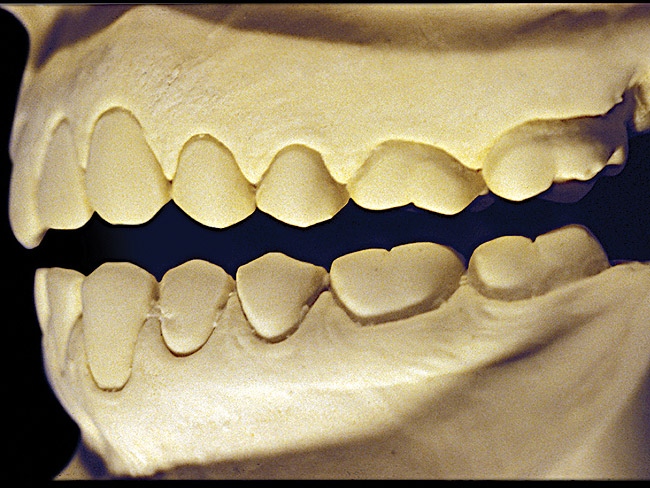

Figure 5  Moderate NCLTS from bruxism, maxillary arch.

Figure 5

The patient shown in Figure 3 and Figure 4 exhibited severe NCLTS from bruxism. Examination of the casts indicated that the NCLTS was progressively greater toward the anterior teeth. Cupping and cratering was not present because there was no secondary cause. Figure 5 and Figure 6 detail another bruxism patient, but to a lesser degree and one with cupping/cratering caused by toothpaste. The cups or craters were not caused from bruxism because the teeth could not touch the bottom of the invaginations. In both featured patients, upon hand-articulating the casts, the NCLTS facets matched up and the diagnosis of bruxism was confirmed.